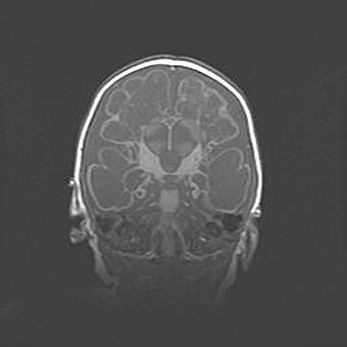

Лейкомаляция с кистозно-глиозной дегенерацией головного мозга.

Возраст: 2 месяца 25 дней

Вес: 6400 г

Окружность головы: 40 см

Срок гестации: 41 неделя

Лейкомаляцию относят к ишемически-гипоксическим повреждениям головного мозга, диагностируемым у новорожденных. При лейкомаляции в головном мозге обнаруживают очаги некроза, возникшие после тяжелой гипоксии и нарушения кровотока. В процессе морфогенеза очаги проходят три стадии: 1) развития некроза, 2) резорбции и 3) формирования глиозного рубца или кисты. Перивентрикулярная лейкомаляция (ПЛ) встречается примерно в 12% случаев среди новорожденных, обычно – у недоношенных детей, причем, частота ее зависит от массы, с которой младенец появился на свет. Наибольшее число малышей страдает лейкомаляцией, если масса при рождении 1500-2500 г.